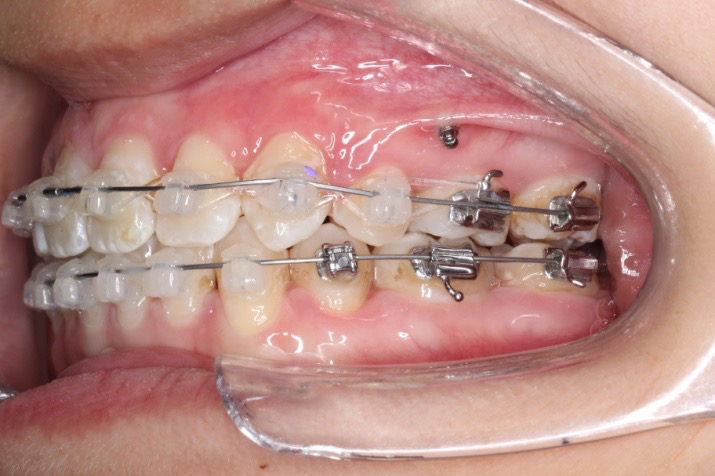

2017.04.28  上0.016*25ss 13、23近远中约5度 v形曲,下0.017*25ss

2017.05.26  磨牙近中倾斜,下颌36、46加power arm

2017.07.25

2017.07.25  上前牙加颈部弹力线

下颌磨牙通过powerarm直立效果明显,下颌整平效果明显